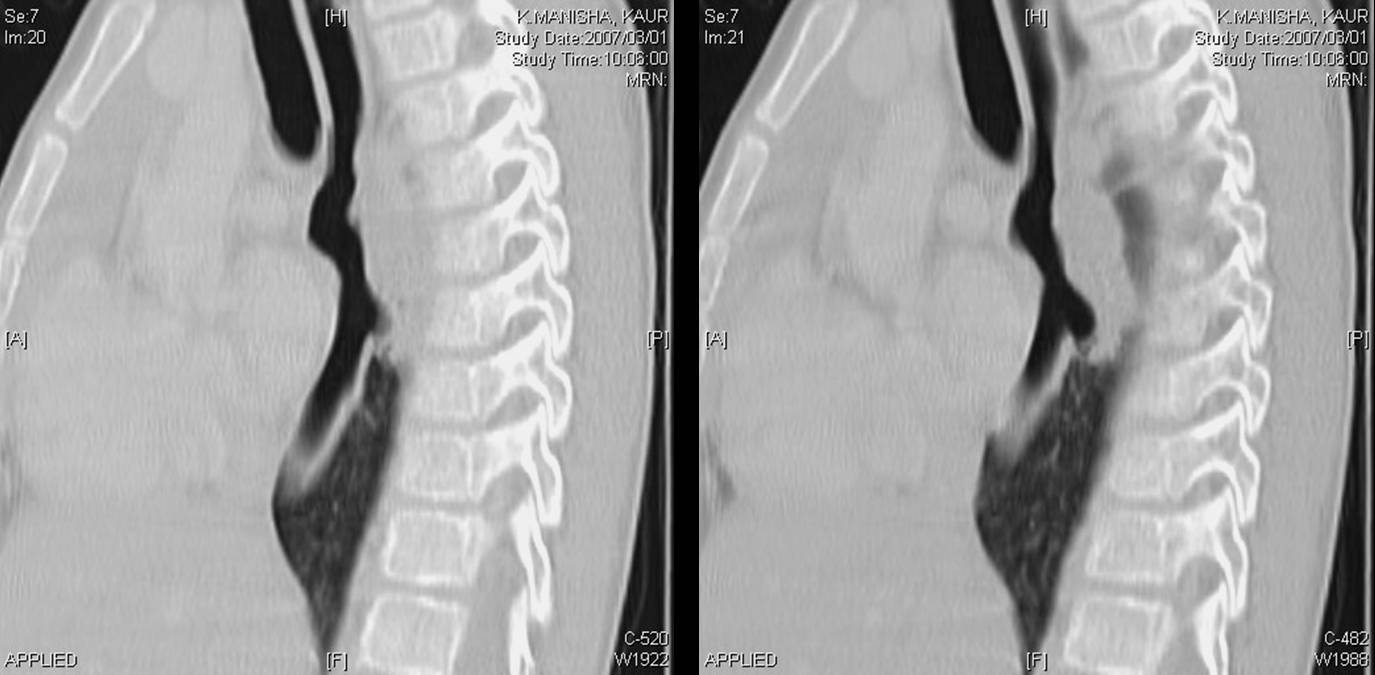

A CT scan of chest was done.

The following screen shows the images from the Chest CT.

| Figure 4-a | Figure 4-b | Figure 4-c |

| Figure 4-d | Figure 4-e | Figure 4-f |